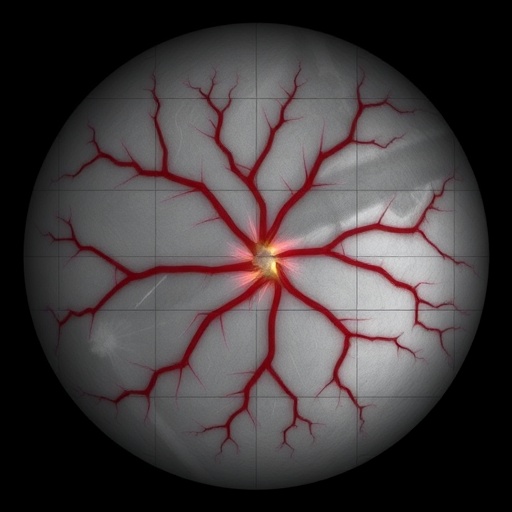

In a groundbreaking study set to advance the field of medical imaging, researchers have unveiled a novel approach to enhance the classification of arteries and veins in retinal images using advanced Y-Net convolutional networks. The significance of this work cannot be overstated as it aims to elevate the accuracy and reliability of retinal imaging diagnosis. The detection and analysis of blood vessels in the retina are critical for identifying various ocular and systemic conditions, including diabetic retinopathy and hypertension.

The retinal structure is a complex and intricate network of blood vessels that is essential for understanding the overall health of an individual. The classification of these vessels into arteries and veins is a vital first step in many diagnostic processes. Traditional methods often fall short in terms of accuracy, which can lead to misdiagnosis or delayed treatment. Recognizing this challenge, the research team developed an innovative solution leveraging Y-Net convolutional networks, a type of deep learning model known for its effectiveness in image segmentation tasks.

The Y-Net architecture is specifically designed to capture fine details in image data while maintaining computational efficiency. Its unique structure enables the model to learn from both local and global features, making it particularly adept at distinguishing between the subtle characteristics of arteries and veins. The integration of this architecture into retinal imaging offers a promising avenue for improving the quality of vascular assessment in clinical settings.